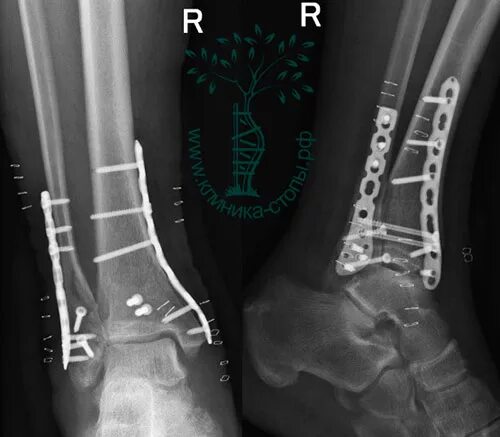

Перелом берцовой кости как разработать